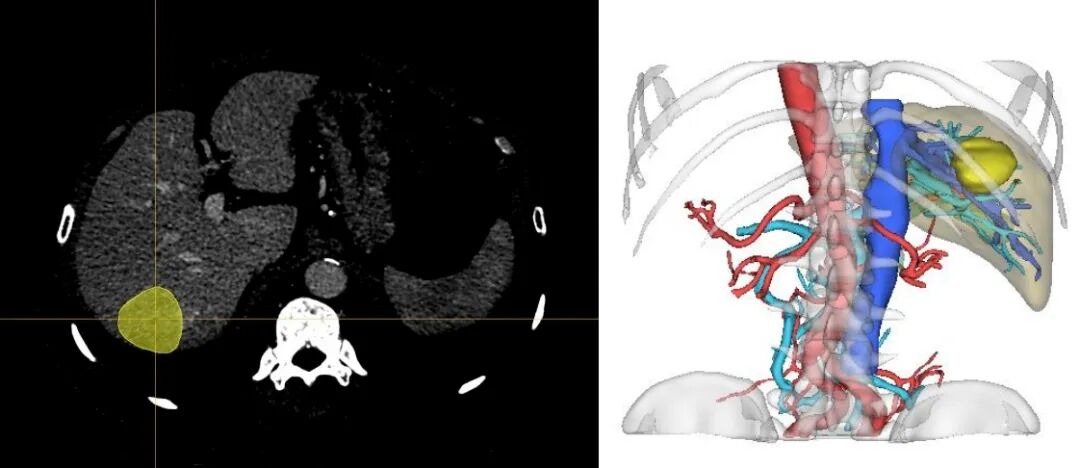

三维重建技术能够将肝脏及肿瘤的二维图像转化为三维立体图像,清晰展示肝脏的解剖结构、血管分布及肿瘤位置,帮助医师更准确地判断病变范围及与周围组织的关系。

阿梵D-CT三维重建结果

2.个体化手术规划

基于三维重建模型,医师可以进行个体化的手术规划,包括切除范围的精确划定、血管变异的分析及处理等,从而减少手术创伤,提高手术成功率。

阿梵D-三维重建效果

3.多角度观察

三维重建模型允许医师从多个角度观察肝脏及肿瘤的解剖结构,有助于选择最优的手术入路,减少对周围组织的损伤。